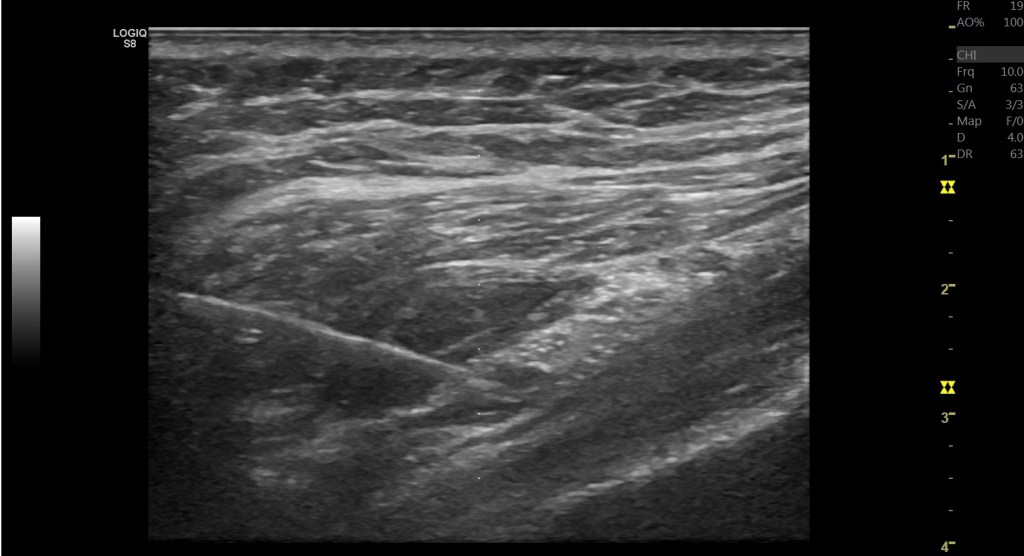

這些都可以在動態超音波底下去區分壓迫到的位置與原因。

另外要注意的是,如果患者有臀深肌與髖後側關節囊或韌帶的緊縮,有時壓迫到坐骨神經的並不是梨狀肌。而是股骨的小結節。此時稱作坐骨股骨夾擠症候群(ischiofemoral impingement)

可以看到在股骨內轉時,其實坐骨神經的張力是會增加的。因此在診斷梨狀肌壓迫坐骨神經前,完整的理學檢查其實還是非常重要,畢竟這些理學檢查都無法100%的診斷,需要結合2-3項理學檢查,甚至透過診斷性注射來確認壓迫的位置。